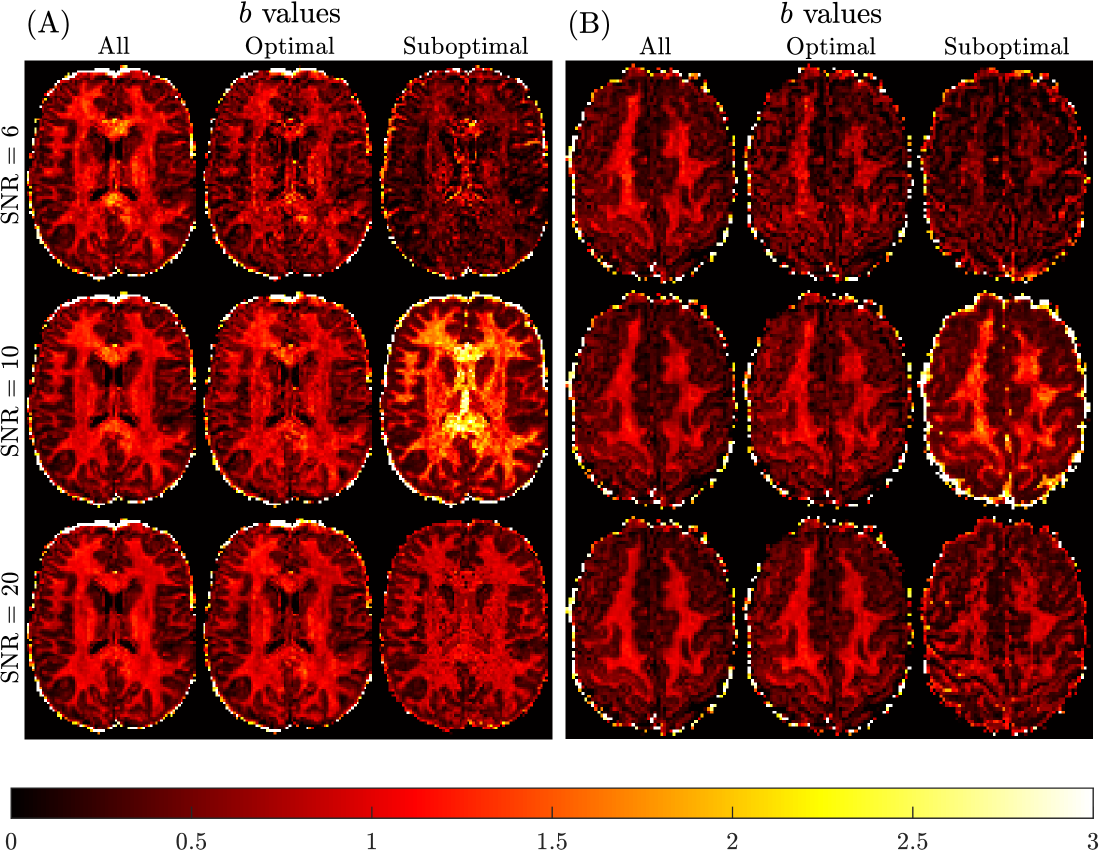

Figure 9 presents the qualitative findings for two subjects generated using all, optimal and sub-optimal b-value samplings with SNR = 6666 (3 non-collinear directions, 6 measurements), 10101010 (8 non-collinear directions, 16 measurements) and 20202020 (32 non-collinear directions, 64 measurements) DW-MRI data. The quality of the mean kurtosis map improves with increasing SNR, and also by optimising b-value sampling. Optimal sampling at SNR = 10101010 is qualitatively comparable to the SNR = 20202020 optimal sampling result, and to the benchmark sub-diffusion results in Figure 6.

Refer to caption

Figure 9: Spatially resolved maps of mean kurtosis shown for two example slices and two different subjects, Subject 3 rescan slice 71 (Panel A) and Subject 5 slice 74 (Panel B), based on SNR reduction of the Connectome 1.0 DW-MRI data. Individual maps were generated using the sub-diffusion model framework (Ksuperscript𝐾K^{*}italic_K start_POSTSUPERSCRIPT ∗ end_POSTSUPERSCRIPT), considering optimal and sub-optimal four non-zero b-value sampling schemes. Here, two b-values with Δ=19 msΔ19 ms\Delta=19\text{ ms}roman_Δ = 19 ms and two b-values with Δ=49 msΔ49 ms\Delta=49\text{ ms}roman_Δ = 49 ms were selected for each case. The optimal b-values were chosen as the best for each SNR shown in Table 1. The sub-optimal b-values were chosen to have an R2=0.3,0.45,0.5superscript𝑅20.30.450.5R^{2}=0.3,0.45,0.5italic_R start_POSTSUPERSCRIPT 2 end_POSTSUPERSCRIPT = 0.3 , 0.45 , 0.5 to be about half of the maximum R2superscript𝑅2R^{2}italic_R start_POSTSUPERSCRIPT 2 end_POSTSUPERSCRIPT, for SNR =6absent6=6= 6 (b=800,1500,200,2300 s/mm2𝑏80015002002300 ssuperscriptmm2b=800,1500,200,2300\text{ s}/\text{mm}^{2}italic_b = 800 , 1500 , 200 , 2300 s / mm start_POSTSUPERSCRIPT 2 end_POSTSUPERSCRIPT), SNR =10absent10=10= 10 (b=1500,3450,6750,13500 s/mm2𝑏15003450675013500 ssuperscriptmm2b=1500,3450,6750,13500\text{ s}/\text{mm}^{2}italic_b = 1500 , 3450 , 6750 , 13500 s / mm start_POSTSUPERSCRIPT 2 end_POSTSUPERSCRIPT) and SNR =20absent20=20= 20 (b=3450,4750,2300,4250 s/mm2𝑏3450475023004250 ssuperscriptmm2b=3450,4750,2300,4250\text{ s}/\text{mm}^{2}italic_b = 3450 , 4750 , 2300 , 4250 s / mm start_POSTSUPERSCRIPT 2 end_POSTSUPERSCRIPT), respectively. The benchmark kurtosis map is provided in Figure 6.

Quantitative verification of the qualitative observations are provided in Table 5. Significant differences in brain region-specific mean kurtosis values occur at the SNR =6absent6=6= 6 level, which are not apparent when SNR =10absent10=10= 10 or 20202020 data with optimal b-value sampling were used. The average errors are relative errors compared to the benchmark kurtosis values reported in Table 2. When using optimal b-values, average errors range from 22% to 43% at SNR = 6, from 13% to 43% at SNR = 10, and from 8% to 20% at SNR = 20, across brain regions. When using sub-optimal b-values, average errors range from 47% to 57% at SNR = 6, from 24% to 102% at SNR = 10, and from 27% to 72% at SNR = 20. Also, the brain region-specific CV for mean kurtosis was not found to change markedly when SNR =10absent10=10= 10 or 20202020 data were used to compute Ksuperscript𝐾K^{*}italic_K start_POSTSUPERSCRIPT ∗ end_POSTSUPERSCRIPT. The result of reducing the SNR to 6666 leads to an approximate doubling of the CV for each brain region. These findings confirm that with optimal b-value sampling, the data quality can be reduced to around the SNR =10absent10=10= 10 level, without a significant impact on the region-specific mean kurtosis estimates derived using the sub-diffusion model.